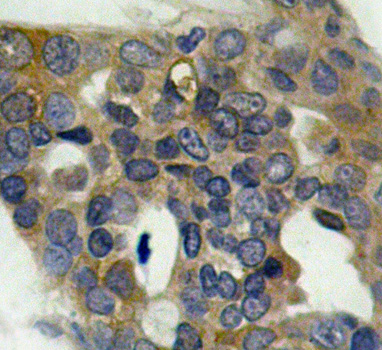

• AP0194: image 2

Immunohistochemical analysis of paraffin-embedded human breast carcinoma tissue using Phospho-MAP3K5-S966 antibody.